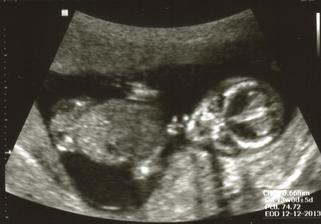

8.8.2013 ... další UTZ a potvrzená HOLČIČKA 🙂) ... má necelých 500g a 26cm ... a já 52,5kg 🙂